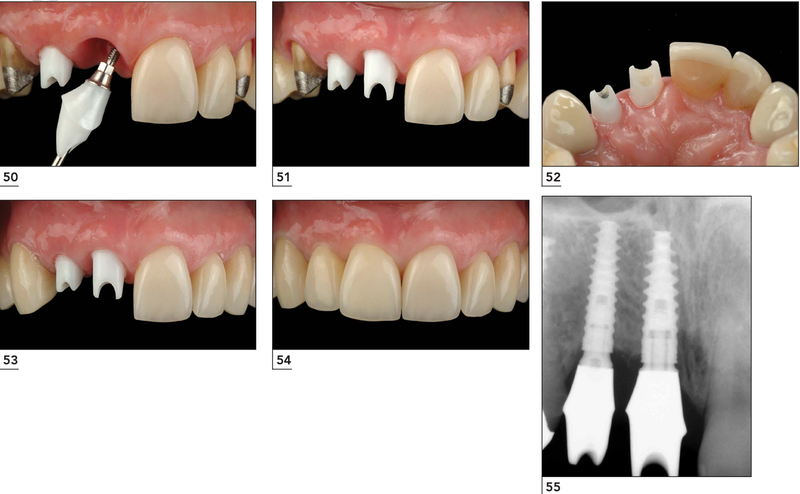

Bước 1. Lấy dấu hàm chế tác trụ phục hình và mão răng sứ

Khoảng 3 - 6 tháng sau cấy ghép, khi trụ Implant đã tích hợp vững chắc với xương hàm, cô chú/anh chị sẽ được hẹn quay lại để lấy dấu răng bằng máy Scan 5D. Quá trình này nhằm ghi nhận chính xác hình dáng, vị trí các răng và đường viền nướu, từ đó chế tác trụ phục hình và mão răng sứ phù hợp.

Tại Lạc Việt Intech, với giải pháp DCT, ngoài trụ phục hình được thiết kế cá nhân hóa theo đường viền lợi, mà các bác sĩ còn sử dụng 3D Pro Multilayer - mão răng giống y đúc răng thật với màu trắng sáng tự nhiên, chuyển sắc tinh tế từ cổ răng đến mặt nhai.

Bước 2: Chế tác Abutment và mão răng sứ

Sau khi lấy dấu, toàn bộ dữ liệu được chuyển về phòng Labo để thiết kế và chế tác Abutment (trụ phục hình) và mão răng sứ. Quá trình này được thực hiện bằng công nghệ CAD/CAM hiện đại, giúp đảm bảo độ chính xác gần như tuyệt đối, đồng thời rút ngắn thời gian chế tác và tạo hình thể răng thẩm mỹ, tự nhiên.

Bước 3: Đặt trụ phục hình cá nhân hóa và mão răng sứ

Khoảng 3 - 5 ngày sau khi lấy dấu, cô chú/anh chị quay lại để gắn trụ phục hình cá nhân hóa và lắp mão sứ. Quá trình này diễn ra trong khoảng 30 phút đến 1 tiếng, bao gồm các bước: đặt trụ phục hình, thử khớp cắn, điều chỉnh lực nhai, lắp mão răng sứ và bịt lỗ kỹ thuật cố định mão. Sau khi hoàn tất, cô chú/anh chị có thể ăn uống nhẹ ngay trong ngày và ăn nhai bình thường sau 24 giờ.